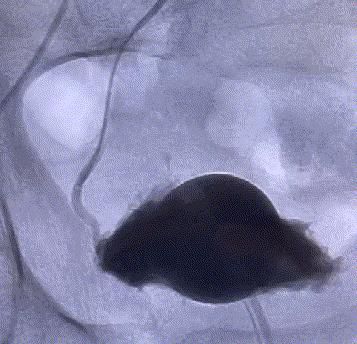

随後,李旭丹主任攜手胡志華主任爲患者實施介入治療,采用改良Seldinger法穿刺股動脈,在DSA引導下經動脈自然腔道,将微導管分别送達雙側髂内動脈進行造影,觀察雙側前列腺動脈分布情況,将微導管超選擇至雙側前列腺動脈,準确置入PVA栓塞材料,成功阻斷前列腺的營養供給,順利完成了治療。

△術後,前列腺供血動脈被成功阻斷。